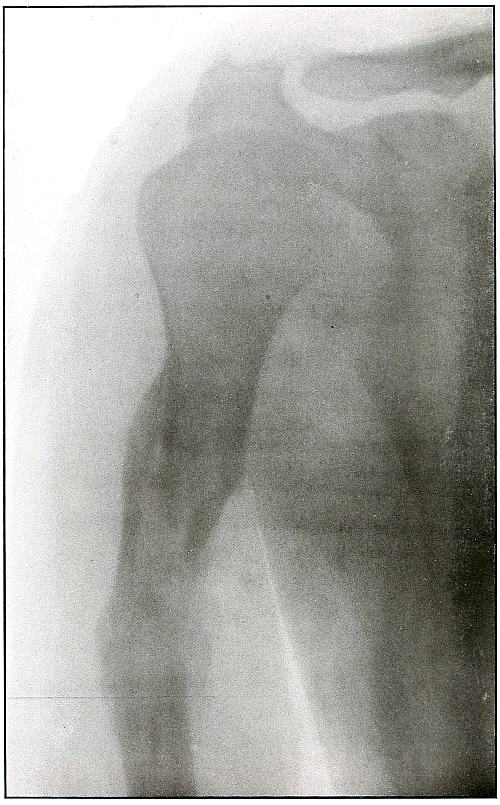

82.[Pg 5] Gunshot wound, shoulder 174

83. Gunshot wound, shoulder 176

84. Gunshot wound, shoulder 178

85. Gunshot wound, shoulder 180